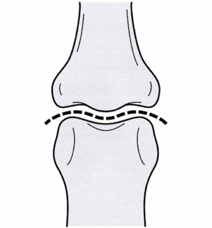

上記の保存治療でも改善ない場合は、手術をお勧めします。手術は図の緑の神経の通り道が狭くなっている部分を切開し圧迫をとる手術です。その際は近隣の手術ができる整形外科病院へ紹介いたします。